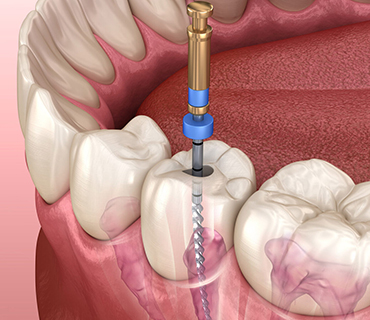

Root Canal Treatment

Root canal treatment is a procedure done when the tooth decay reaches the pulp causing pain & inflammation.

The procedure is

- Removal of infected tooth structure

- Clearing & Disinfection

- Filling with an inert material

- Restoration with crown or cap

Root canal treatment is a common dental procedure that helps save an infected or damaged tooth. However, many people have questions and concerns about this treatment. In this blog post, we will provide answers to some of the most frequently asked questions about root canal treatment. By addressing these concerns, we aim to alleviate any fears or misconceptions you may have, helping you make informed decisions about your dental health.

What is a root canal treatment?

A root canal treatment, also known as endodontic therapy, is a dental procedure performed to save a tooth that has an infected or inflamed dental pulp. The dental pulp, which consists of nerves, blood vessels, and connective tissue, is located inside the tooth's root canals.

Why might I need a root canal?

How is a root canal procedure performed?

The root canal procedure typically involves the following steps:

Is a root canal painful?

Contrary to popular belief, root canal treatments are performed under local anesthesia, ensuring that you won't experience any pain during the procedure. Modern techniques and advances in dentistry have made root canal treatments more comfortable and efficient than ever before.

How long does a root canal treatment take?

The duration of a root canal treatment varies depending on the complexity of the case and the tooth involved. In general, a root canal procedure can be completed in one or two appointments, lasting approximately 60 to 90 minutes each. Complex cases may require additional visits.

What should I expect after a root canal?

After a root canal treatment, you may experience temporary sensitivity or mild discomfort, which can be managed with over-the-counter pain relievers. It is essential to follow your dentist's instructions regarding oral care and attend any necessary follow-up appointments for optimal healing and restoration.

Are there any alternatives to a root canal?

In cases where a tooth is severely damaged or infected, a root canal treatment is often the best option to save the tooth. Extraction may be considered as an alternative, but it is generally recommended to preserve natural teeth whenever possible. Extracted teeth may require additional dental procedures, such as dental implants or bridges, to restore functionality and aesthetics.

How successful is a root canal treatment?

Root canal treatments have a high success rate, typically ranging from 85% to 97%. With proper oral care, including regular brushing, flossing, and dental check-ups, the treated tooth can last a lifetime.

Can a root canal treatment be performed on any tooth?

Root canal treatments can be performed on most teeth, including incisors, canines, premolars, and molars. However, in some cases, tooth extraction may be the only viable option if the tooth's structure is severely compromised.

Are there any risks or complications associated with root canal treatment?

As with any dental procedure, there are potential risks and complications associated with root canal treatment. These may include infection recurrence, fracture of the tooth, or damage to nearby structures. However, with proper technique and adherence to sterile protocols, the risk of complications is minimal.